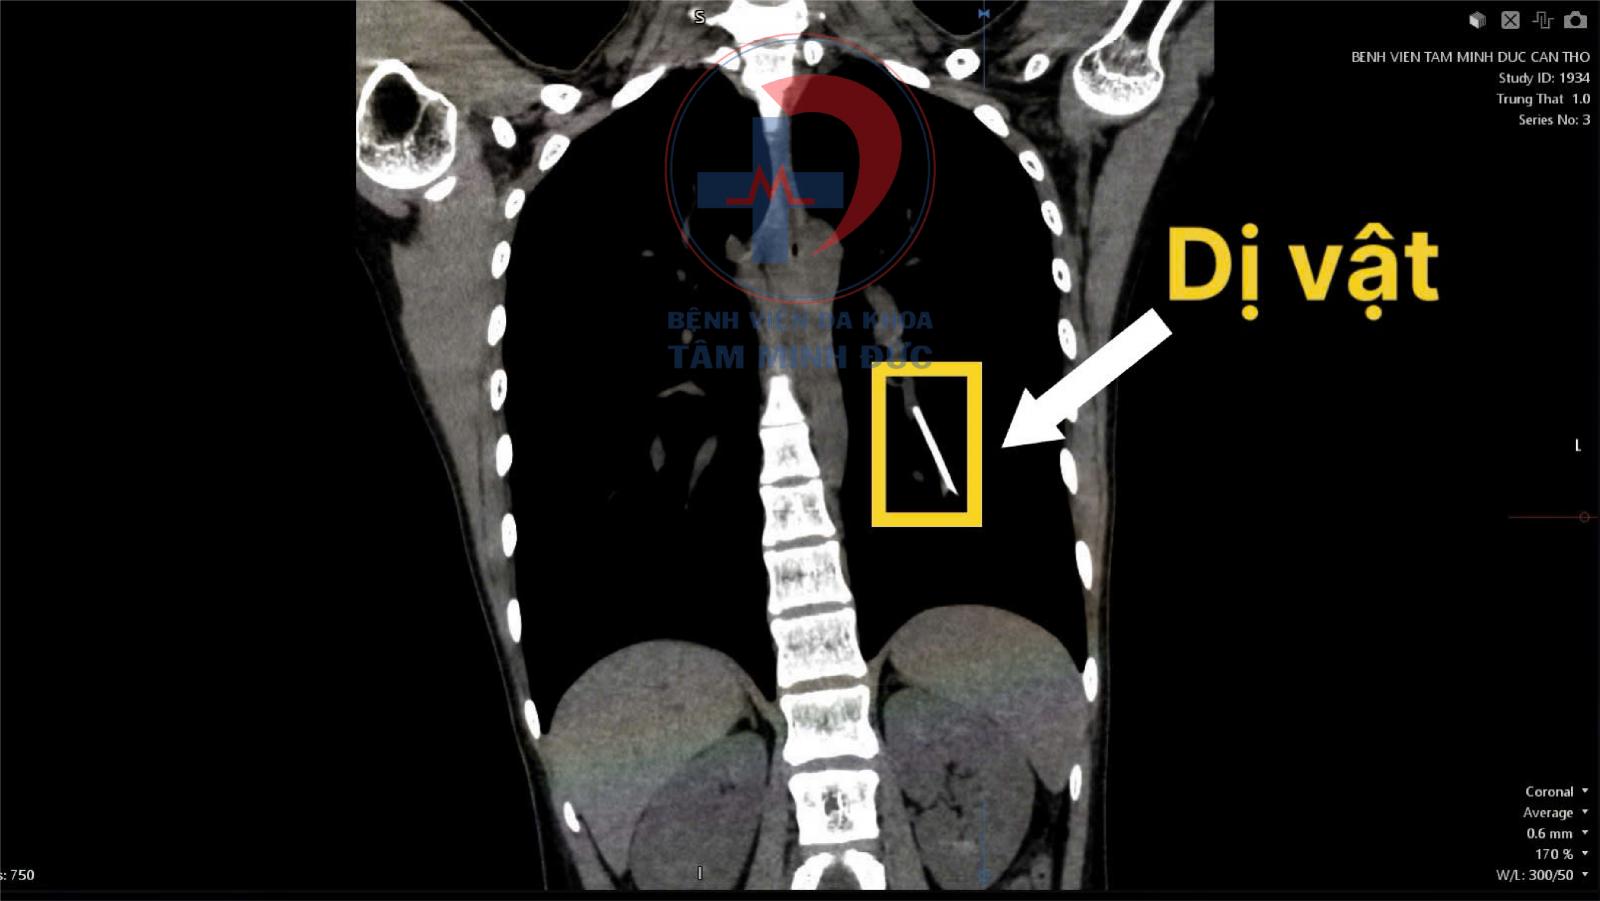

Qua thăm khám và chụp CT ngực có tiêm thuốc cản quang, kết quả cho thấy một dị vật dạng que nằm trong nhánh động mạch nuôi thùy dưới phổi trái. Hình ảnh có mật độ kim khí phù hợp với que tránh thai. Đây là biến chứng lạc chỗ cực kỳ hiếm gặp, nhưng đã từng được ghi nhận ở một số nơi trên thế giới.

Phát hiện chủ yếu dựa vào chẩn đoán hình ảnh như X-quang, CT-scan.